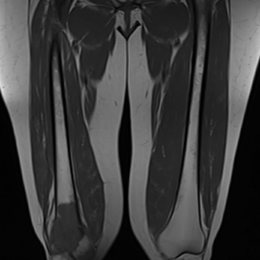

Radiographic imaging is used to help form a diagnosis. These include X-Ray, MRI, CT and Bone Scans

An example of an UPS MRI is shown.

102C) Coronal T1 MRI Of Right Femur MFH